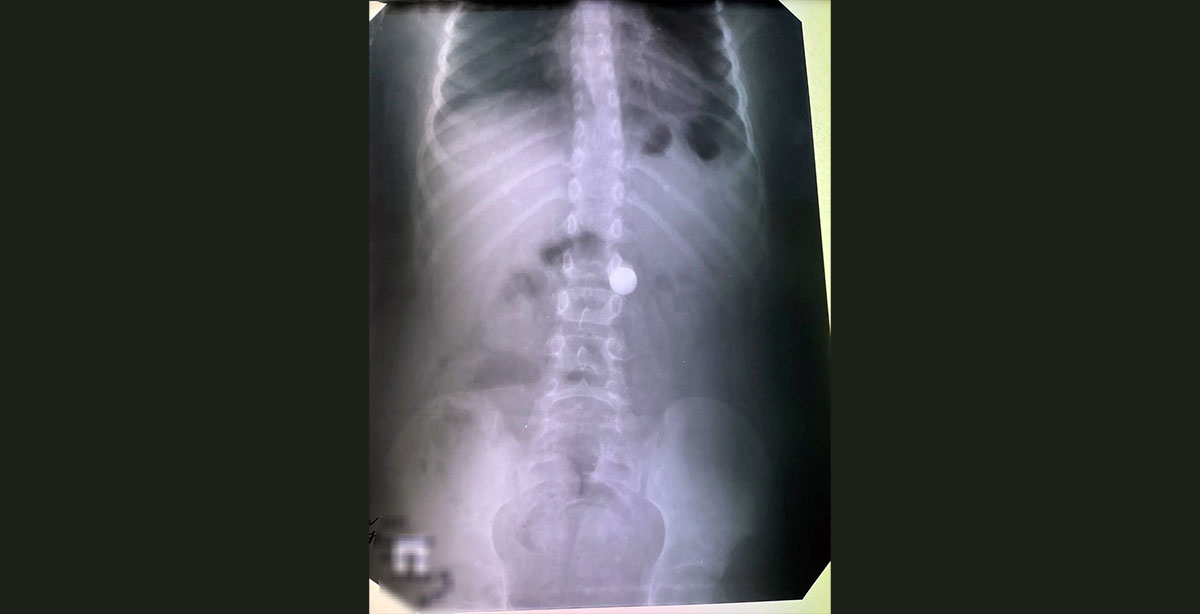

Как рассказала заведующая эндоскопическим отделением Элла Анатольевна Бобрышева, за весь праздничный период поступил лишь один ребёнок. Восьмилетний мальчик проглотил металлический шарик диаметром в один сантиметр, который был успешно извлечён. Это минимальный показатель за последние годы, когда в отделении ежедневно приходилось извлекать монеты, детали игрушек и рыбные кости.